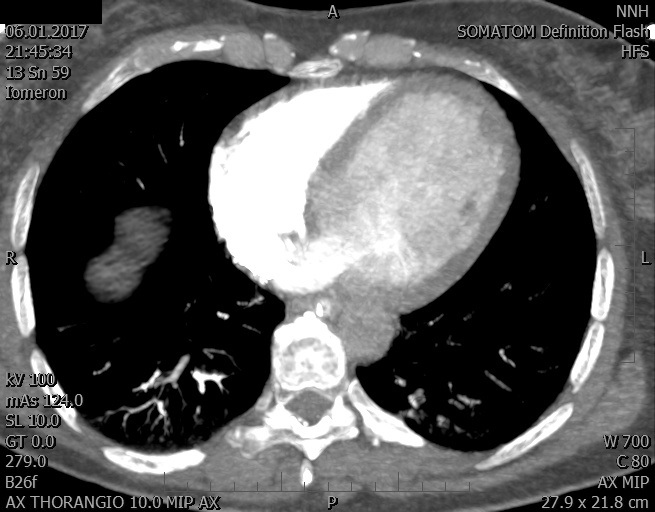

Video 1 - Akutní koronarografie prokázala normální nález na věnčitých tepnách s výjimkou suspekce na lehký spasmus na pravé koronární tepně.Echokardiograficky byla zjištěna těžká dysfunkce dilatované levé komory s nezvětšenou pravou komorou (video 2).

Video 2 - Echokardiograficky byla zjištěna těžká dysfunkce dilatační levé komory s nezvětšenou pravou komorou.Pro nejasnou příčinu zástavy jsme provedli i vyšetření výpočetní tomografií (CT), které vyloučilo plicní embolizaci (série 1 - soubory na konci článku). V den přijetí při přetrvávající oběhové nestabilitě byla nemocná opakovaně defibrilována pro fibrilaci komor se stabilizací rytmu po podání amiodaronu a mesocainu. Dle hemodynamických měření se jednalo o těžký kombinovaný šok. Vstupní laboratorní vyšetření bylo bez větších pozoruhodností. Posléze jsme doplnili anamnézu od příbuzných a zjistili, že pacientka užila do dvou hodin před srdeční zástavou první tabletu amoxicilinu na lehký respirační infekt. Při nevýtěžnosti vstupních vyšetření a nových anamnestických informacích jsme doplnili 14 hodin po kolapsu vyšetření koncentrace tryptázy v séru, která byla extrémně zvýšena (tabulka 2), což nás vedlo k podezření na anafylaxi.